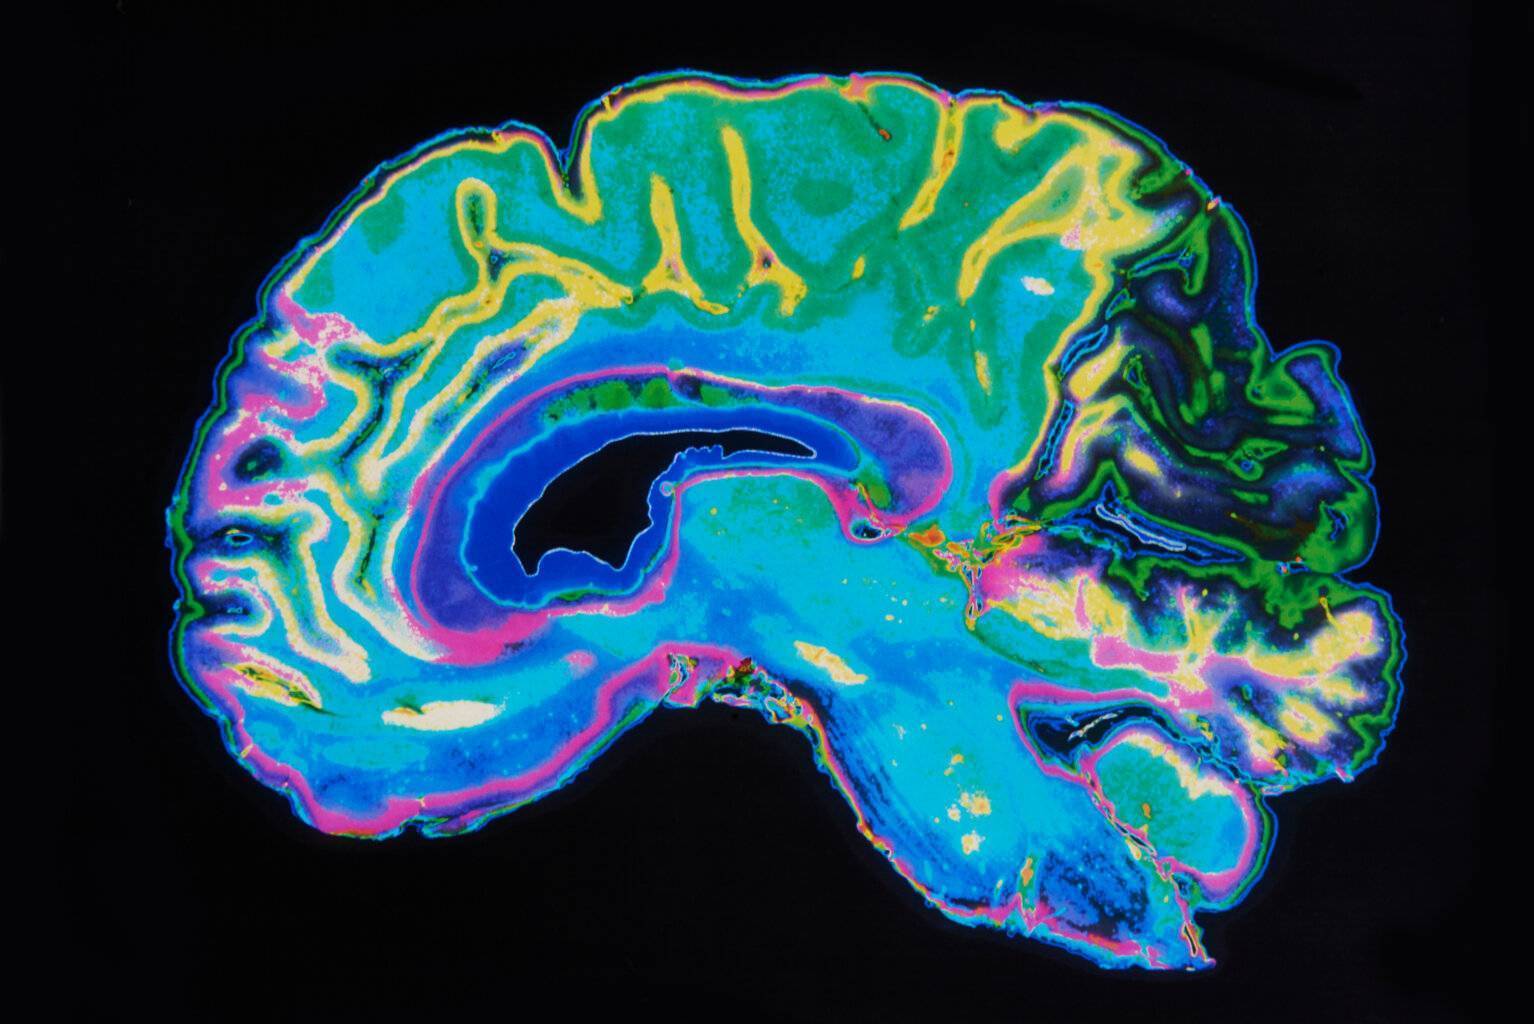

Magnetresonanztomografie (MRT)

Die MRT erzeugt mittels starker Magnetfelder und Radiowellen hochauflösende Bilder von inneren Strukturen des Körpers. Im Gegensatz zur CT verwendet die MRT keine Strahlung, sondern basiert auf der Wechselwirkung von Wasserstoffatomen im Körper mit den Magnetfeldern. Sie ist besonders effektiv bei der Darstellung von Weichteilen wie Gehirn, Rückenmark, Muskeln, Gelenken und inneren Organen. MRTs werden oft zur Diagnose von Erkrankungen des Gehirns, der Wirbelsäule, Gelenkverletzungen sowie bei Tumorerkrankungen eingesetzt. Sie ist zudem für wiederholte Untersuchungen geeignet, da keine Strahlenbelastung erfolgt.